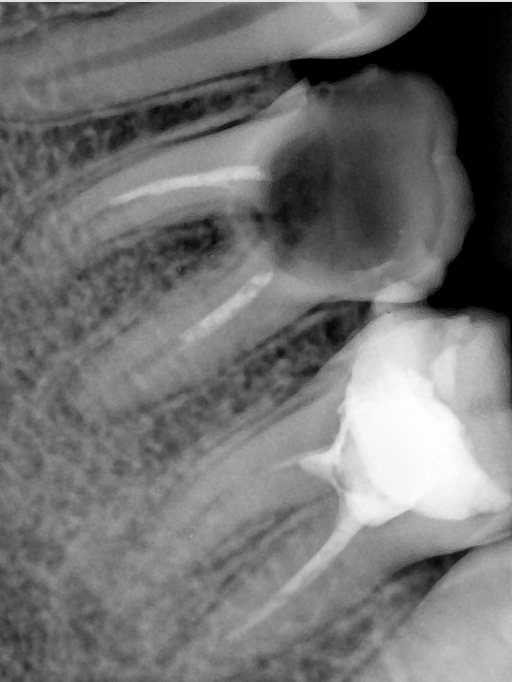

CR/DR 牙齿分割阶段记录

当前进展

- 完成了 CR/DR 牙齿相关分割训练

- 当前结果已经达到阶段预期,但仍有细节问题需要继续处理

相关测试

遇到的问题

- 训练过程中出现过 mask 下移问题

- 部分结果会出现 box 填充异常

- mask 边缘仍然有比较明显的锯齿感

第二版算法问题测试